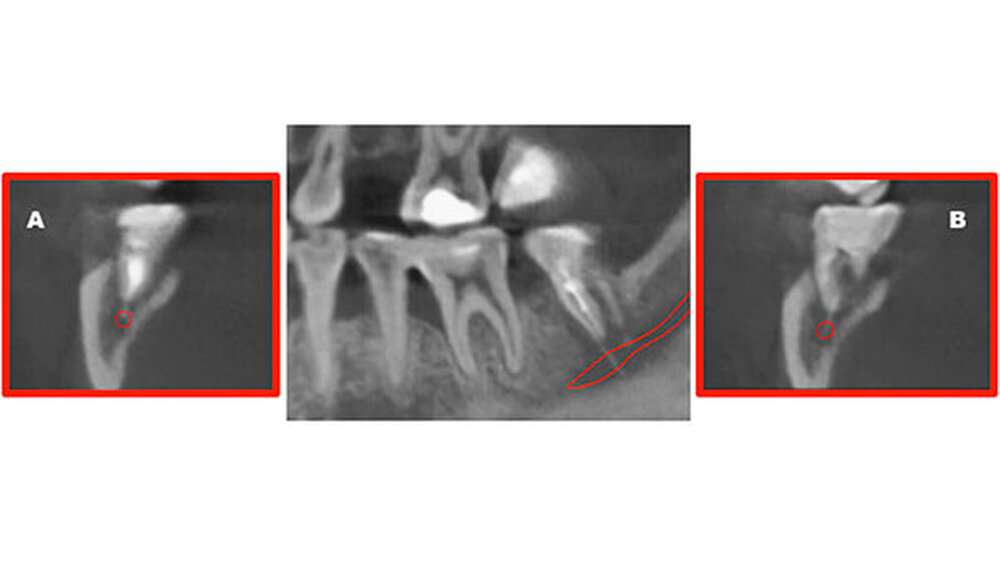

Die dreidimensionale Darstellung des Unterkiefers rechts mittels digitaler Volumentomografie (DVT, Abbildung 4) vervollständigte den Nachweis von röntgenopakem Material im Bereich der Wurzelspitzen des Zahnes 47 mit direktem Kontakt zum Nervus alveolaris inferior. Die Rücksprache mit dem ausländischen Behandler ergab die Information, dass es sich bei dem Füllmaterial um Guttapercha zusammen mit einem paraformaldehydhaltigen Zement handelte.

Im Bereich der zweiten Molaren im Unterkiefer ist die knöcherne Distanz zwischen den Apices und dem Nervkanal - wie im beschriebenen Fall - oftmals geringer als ein Millimeter, was zu derartigen Schäden prädisponieren kann [Pogrel, 2007].